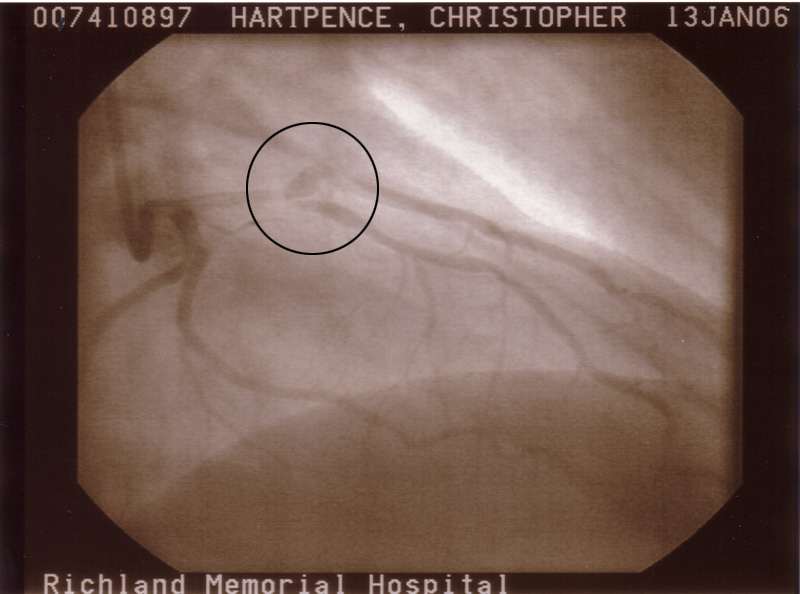

At this point I am getting aggravated. I see him everyday. He was getting worse. He was hurting while we were in the office right then. So he told the Doctor that he was hurting now. So they did yet another EKG and had the stress test results sent to the ASAP and sure enough they were abnormal and he was admitted to the hospital at about 2 o'clock. He was sent straight to the cath lab where they went in to take pics. (Pics to follow) And if something was found they were going to fix it right then.

They found something. Somthing that was reffered to as a plaque rupture. Plaque in your arteries is like the buildup on your teeth. Apparently that goop ruptured and got all over everywhere and clogged up two different places that kind of branch off.

They placed two stints in those and ballooned another place.